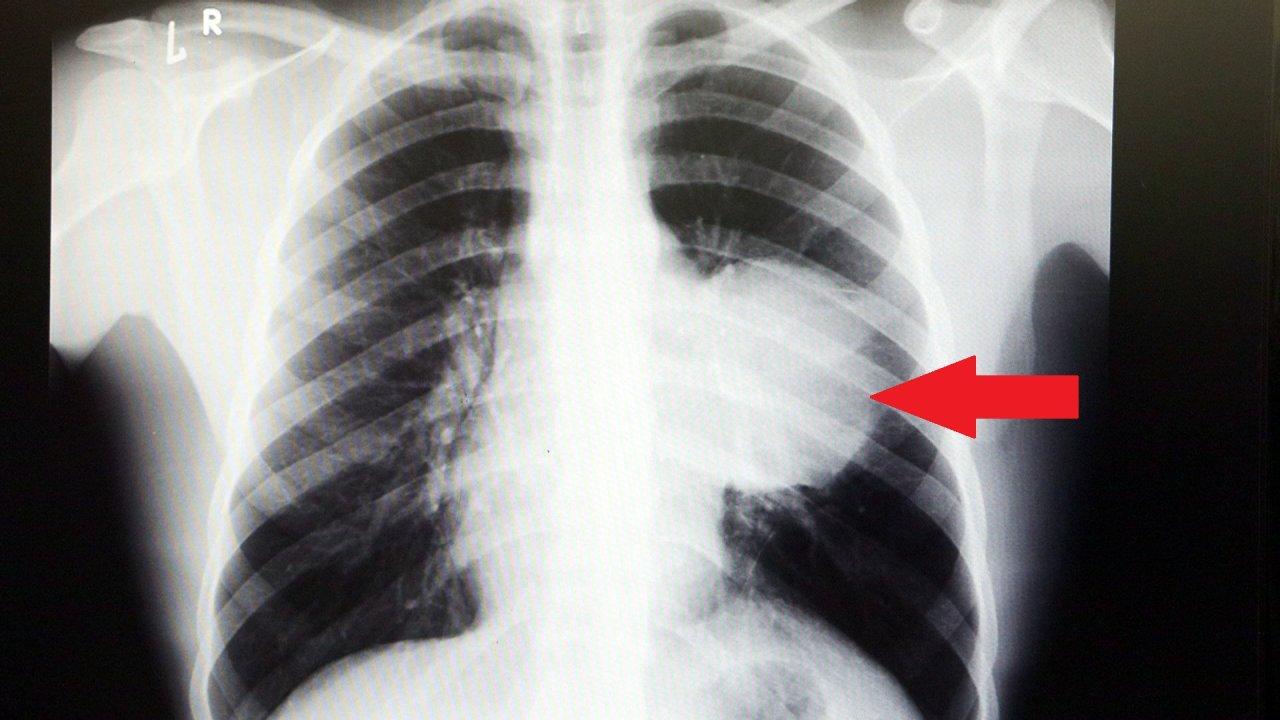

İstanbul'da yaşayan 21 yaşındaki Burak Aktaş, Temmuz ayında işe girmek üzere sağlık raporu almak için hastaneye gitti. Herşey yolundaydı ve raporunu alarak iş başı yaptı. Bir ay geçmeden nefes darlığı, halsizlik, öksürük gibi şikayetlerle başka bir hastaneye gittiğinde ise ilk şoku yaşadı. Sol göğüs boşluğunda portakal büyüklüğünde bir kitle tespit edilmişti. Yapılan biyopside tümörün akciğer kaynaklı olmadığı, henüz cenin aşamasında eşey hücrelerinin farklılaşmasıyla gelişen "immatür teratom" teşhisi kondu. Kitleyi küçültmek için kemoterapi uygulansa da tam tersine tümör 2 ay içinde neredeyse 10 katına çıktı ve büyük bir karpuz boyutuna ulaştı. Sol akciğerinin yüzde seksenini kağıt gibi ezen, kalbini göğüs duvarında 12 santim sağa kaydıran ve hem kalbe hem beyne giden ana damarlara baskı yapan 6.5 kilo ağırlığındaki dev tümör, Koşuyolu Yüksek İhtisas Eğitim ve Araştırma Hastanesi Göğüs ve Kalp Damar Cerrahisi ekiplerinin birlikte girdiği operasyonla başarılı şekilde çıkarıldı. Operasyon sırasında Aktaş'ın kalbi normal yerine çekildi, sol akciğerin üst lobu alındı, ezilen alt lobu ise anestezi ekipleri tarafından pozitif basınçla yeniden şişirildi. Ameliyatı gerçekleştiren ekipten Prof. Dr. Erdal Taşçı, Aktaş'ın göğüs boşluğunun neredeyse tamamını kaplayan 6,5 kiloluk tümörün teratom (eski Yunancada "canavar tümör') türlerinden biri olduğunu ve embriyonik hücrelerden kaynaklandığını kaydetti.

Prof. Dr. Erdal Taşçı, "Bundan 2,5-3 ay öncesine kadar hiçbir problemi olmayan, hayatını normal devam ettiren bir delikanlı Burak. Göğüs ağrısı öksürük ve nefes darlığı şikayetiyle sağlık kuruluşuna başvuruyor. Orada yapılan tetkiklerinde sol göğüs boşluğunda akciğerinden kaynaklanmayan portakal büyüklüğünde bir kitle tespit ediliyor ve immatür teratom tanısı konuyor. 2 ay arayla yapılan tetkiklerinde ve arada cerrahi öncesi küçültme amaçlı kemoterapi almasına rağmen, portakal büyüklüğündeki tümör, irice bir karpuz büyüklüğüne, yaklaşık 6 kilo 300 grama kadar ulaşıyor. Göğüs boşluğunda kemik kafesi içinde olduğu için, itebileceği iki organ var; biri kalp, diğeri de akciğerler. Soldan sağa doğru büyüdüğü için kalbi tamamen göğüs boşluğunun sağ tarafına itmiş ve kalbe giren ve kalpten çıkan bütün büyük damarları da yer değiştirmenin etkisiyle bükülmüş durumdaydı. Bu nedenle vücuduna yeterince kan gitmiyordu. Ağustos ayının başında portakal büyüklüğündeyken kitle Eylül sonuna irice bir kavun, Ekim ayına geldiğimizde ise bir karpuz büyüklüğüne ulaştığı için, kitlenin büyüme hızı bizi acilen ameliyat yapmaya yöneltti. Yaklaşık 8-10 kat hacimsel olarak artmıştı. Sol akciğer tamamen ezilmiş ve kağıt haldeydi, alt lobu anestezi ekibimiz yüksek basınç uygulayarak tekrar şişirdi. Çok fazla vaktimiz yoktu, kitle basısından dolayı yaşamla bağdaşmayacağından dolayı hızlı hareket etmek zorundaydık. Bize geldikten üç gün sonra hemen ameliyata aldık çünkü tümörden ziyade onun yaptığı baskıdan kaynaklı hayati riski vardı" dedi.

Normalde kalbin özellikle alt ucunun göğüs boşluğunda, iman tahtası orta çizgi kabul edilirse, sola bakar şekilde durduğuna dikkat çeken Prof. Dr. Taşçı, sözlerini şöyle sürdürdü: "Ama bu hastada yaklaşık 12-13 s santimlik kalbin alt ucununu yer değiştirmesi ve kalbe giren çıkan bütün damarlar bükülüp kan akımı bozulmuştu. Kalp Damar Cerrahisi ekibi de bizimle beraber ameliyata girdi. Sol akciğerin üst lobu artık geri dönüşümsüz olarak ezildiği için çıkarmak zorunda kaldık. Kalbi tekrar eski pozisyonuna getirdik. Ameliyat sonrası çok çabuk toparladı. Koşuyolu ailesi olarak böyle büyük bir vakanın altından başarıyla çıktığımız için de ayrıca çok gururluyuz. Bundan sonra onkolog arkadaşlarımız hastamızın yaşamına çok olumlu dokunuşlar yapacak. İmmatür teratom genelde embriyojenik çağda gelişim gösteren germ hücrelerinin farklılaşmasıyla büyür. Vücudun herhangi bir yerinde gelişebilir ve içinde saç, diş, kemik artıkları, jölemsi kıvamda maddeler bulundurabilen bir tümör çeşididir. Kombine tedavilerde çok iyi sonuçlar alınıyor. Bu çocuğumuzu ileride güzel bir hayat bekliyor."